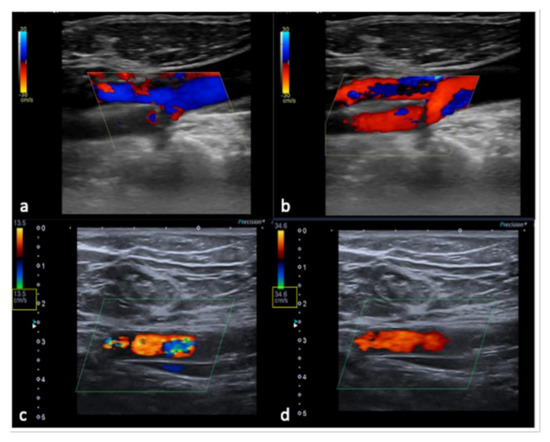

3.3. US-Setting Errors

To avoid errors, a thorough understanding of the functionality and underlying mechanics of the US equipment is required. The goal should always be to produce the highest possible image quality by employing a check-list procedure to configure the correct system settings as well as the correct Doppler parameters, which are critical for interpreting clinical US findings (Table 2, Figure 14 and Figure 15) [6,9,10,11,12].

Figure 14. Flow sampling error with anomalous steering (a) misinterpreted as occlusion of the internal carotid artery; after steering correction (b) a normal artery patency is evident. False aliasing (c) and its correct setting (d) by changing the detection parameters upwards of the flow rate (yellow box, c,d).